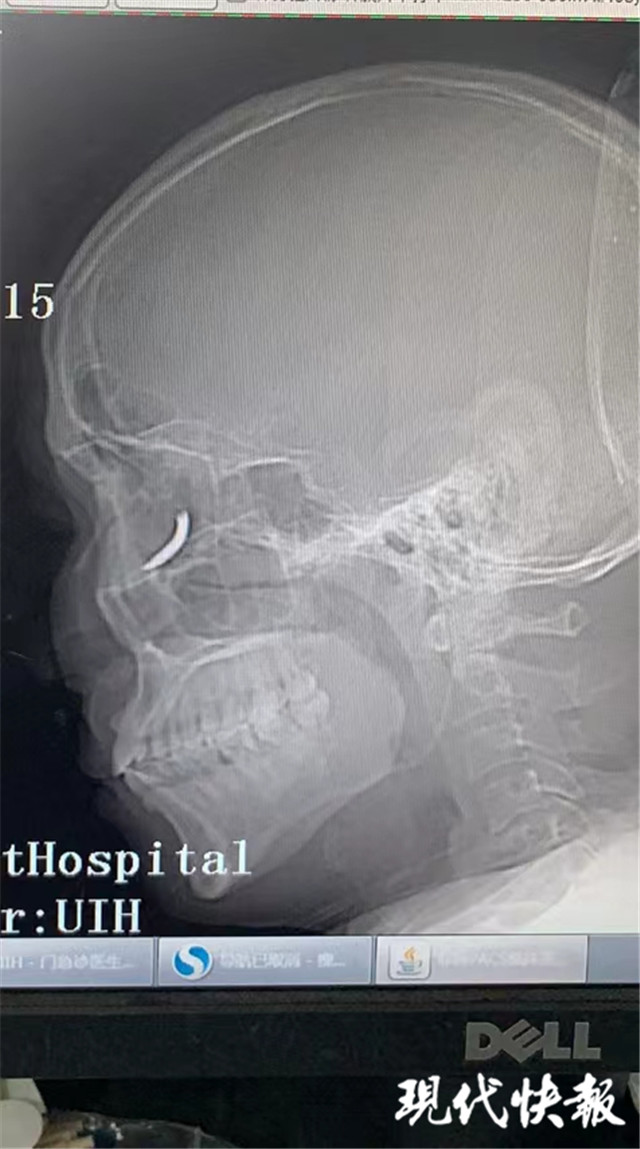

(通訊員 孫忠河 記者 梅書華)鐵釘扎入眼眶,卻不疼不癢,這是怎么回事?三天前,王師傅在溧水的建筑工地干活時,突然感覺有異物進入眼內,但沒當回事,后來出現頭暈才就診,沒想到是鐵釘扎入了眼眶。南京市第一醫(yī)院醫(yī)生通過半小時手術,順利將一根長約一公分的鐵釘取出。

“當時在敲鐵釘,感覺什么東西進眼睛里了,但沒影響視力,還以為是水泥灰之類的。”三天前,王師傅眼中進入異物,感覺頭暈不適后,去當地醫(yī)院就診,拍了X光片后,竟然發(fā)現自己眼眶內有一個鐵釘樣的異物。

隨即,王師傅趕到南京市第一醫(yī)院眼科就診,眼科門診曹雪倩醫(yī)生接診后,立即完善CT等相關檢查。剛準備休息的眼科醫(yī)生范偉杰,立即與副主任醫(yī)師趙貴陽聯合研究這個特殊的病例。專家們發(fā)現這枚鐵釘不偏不倚正好扎進病人的眼眶里,但是眼眶內解剖結構復雜,要在盡可能保護正常組織結構的情況下完成探查并取除鐵釘,手術難度較大。

范偉杰與趙貴陽反復討論后,制定了詳細周密的手術方案,最終以局麻下、眼袋美容切口進入,順利取出了一根長約一公分的鐵釘。整臺手術耗時半小時,手術過程中沒有損傷到眼球壁和視神經,但醫(yī)生發(fā)現因為鐵釘的侵入,視網膜周邊有出血,所以做了視網膜光凝。術后視力1.0,面部看不出瘢痕。王師傅的眼球終于安全保住了。